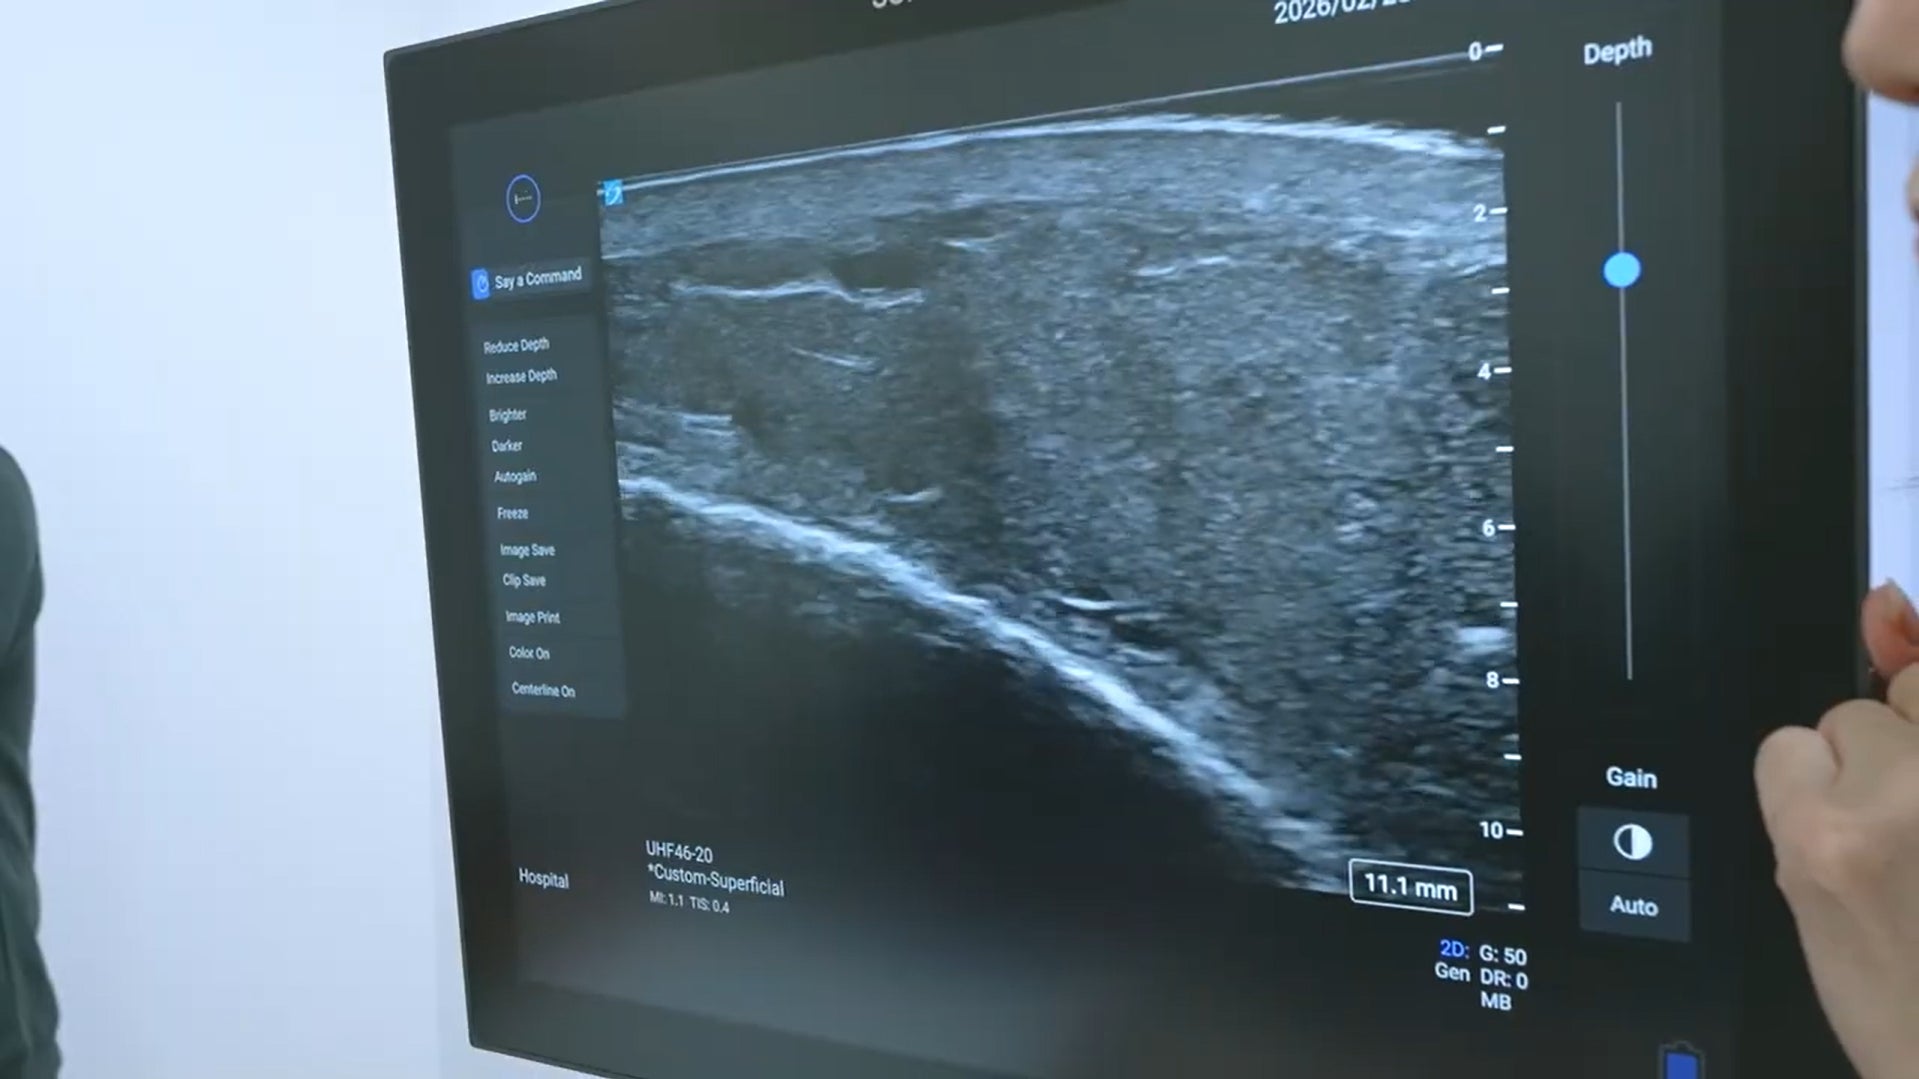

そこで導入されたのが、超高周波によりリンパ管や微細血管を高精細に描出する「Sonosite LX(ソノサイト エルエックス)」です。本機は、従来より高い周波数帯域を用いることで浅層から深部までを高精細に描出できる超音波画像診断装置です。皮下のリンパ管や微細血管といった極めて細い構造を鮮明に可視化します。音声操作機能を備え、画像の静止や条件調整をハンズフリーで行うことが可能です。

説明会では、片脚にリンパ浮腫を抱える患者さんの協力を得て実機デモンストレーションが行われました。まず浮腫のある脚にプローブを当てると、モニター上に血管構造が映し出されました。永尾院長は画面を指し示しながら、静脈とリンパ管の位置を明確に説明します。

「ここに静脈があります。そして、この細い走行がリンパ管です」

続いて健常な側の脚にもプローブを当てると、浮腫のある側とは異なる構造が描出されました。リンパ管の走行や周囲組織の状態の違いが視覚的に確認され、左右差が明確に示されました。

デモの最中、永尾院長は両手をプローブに添えたまま音声で指示を出します。

「Freeze」→ 画像が瞬時に静止します。

「Color」→ 血流がカラー表示に切り替わります。

「Gain up」→ 明るさが調整され、構造がさらに鮮明になります。

操作のたびに手を離す必要はありません。声だけで画像が止まり、カラー表示に変わり、条件が調整されます。診断の流れを途切れさせることなく、画面上の情報が整理されていきます。視覚情報をその場で確認し位置を示すという一連の過程は、熟練医の経験値に可視化という確信が重なり、診療の判断をより明確にしていく様子を示していました。